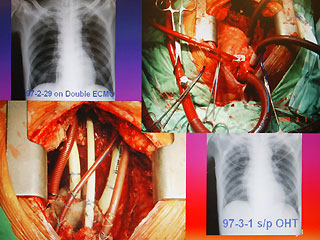

報(bào)道說,現(xiàn)年60歲的陳先生,2月初因發(fā)現(xiàn)感染細(xì)菌性心內(nèi)膜炎,致使整顆心臟感染嚴(yán)重,從奇美醫(yī)院轉(zhuǎn)到臺(tái)大醫(yī)院之后,經(jīng)家屬同意,決定進(jìn)行全心臟摘除,然后置入葉克膜維持生命。陳先生最后靠著葉克膜撐過16天,奇跡式活下來,于今天順利出院。

臺(tái)大醫(yī)院心臟血管外科教授王水深率領(lǐng)團(tuán)隊(duì)執(zhí)行這個(gè)艱難的手術(shù)。他說,陳先生心臟的三尖瓣膜等處已被細(xì)菌噬光,無法修補(bǔ),最后“走投無路”之下,決定先摘除心臟,而家屬的決定也需要相當(dāng)大的勇氣。

王水深說,摘除心臟時(shí)沒人能保證有心臟可換,而靠葉克膜體外維生系統(tǒng)通常也只能維持7天左右,但陳先生靠著兩套葉克膜奇跡式的撐過16天,克服感染及排斥,又能幸運(yùn)的等到心臟捐贈(zèng)者,他強(qiáng)調(diào),翻遍文獻(xiàn)可說史無前例。(周先)